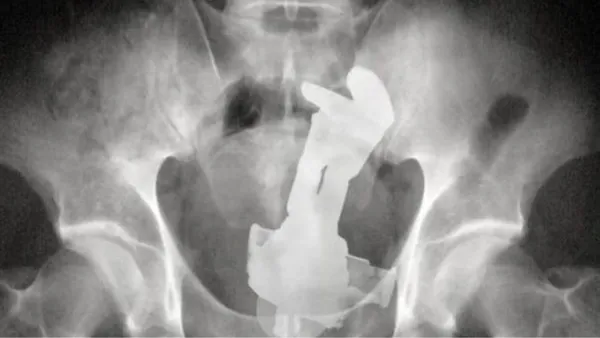

Voor het programma Jackass deed Ryan Dunn ook een duit in het (menselijke) zakje. In de eerste bioscoopfilm uit 2002 slikt hij als huis-tuin-en-keukenstunt een dinky toy door met behulp van een condoom en een handvol glijmiddel. Vervolgens meldt hij zich bij de radioloog.

De grote grap moest zijn dat er een dinky toy op de röntgenfoto te zien was en dat lukte. Na de opnames werd het autootje operatief verwijderd. De röntgenfoto mocht Dunn als trofee meenemen. Dus eind goed al goed.

Overigens is deze röntgenfoto van Dunn tegenwoordig te bewonderen in Nederland. De Nederlandse advocaat en kunstverzamelaar Aernoud Bourdrez vond de röntgenfoto namelijk zo geweldig dat hij Dunn benaderde met het voorstel de foto te ruilen voor een gifgroene DAF 46.

Dunn ging akkoord en sindsdien is de foto te bewonderen in de galerie van Bourdrez in Amsterdam. Dunn zelf is nergens meer te bewonderen. Op 20 juni 2011 werd een auto, maar dan iets groter dan een dinky toy, Dunn alsnog fataal. Hij kwam die dag om het leven toen hij ermee tegen een boom reed.